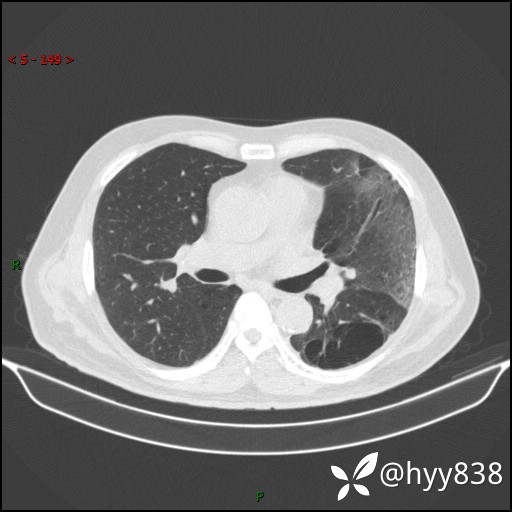

一周后胸部CT